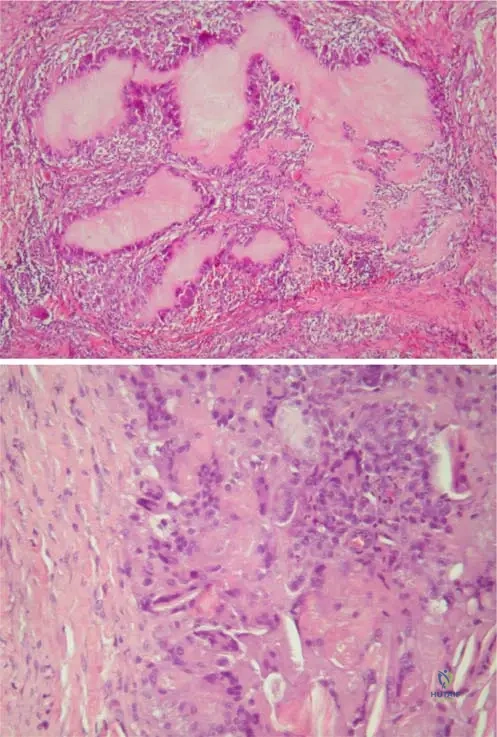

A biopsy of a subcutaneous nodule from a 70-year-old male with chronic gout is sent for histopathological examination. Under the microscope, a characteristic feature of tophus formation is observed. What does the eosinophile-stained amorphous central area of a tophus represent?

Rationale: The clinical context for Fig. 7.6 a states, "Tophus formation is characteristic of gout: eosinophile-stained amorphous central area represents the urate crystals, which dissolved in processing through waterbased solutions." This directly identifies the nature of the central amorphous area. Fibrinoid necrosis is associated with rheumatoid nodules, and calcium deposits with pseudogout or other calcific conditions.

Histopathological examination of a tophus from a 65-year-old male reveals a characteristic cellular reaction surrounding the central amorphous area. What type of cellular reaction is typically observed in response to urate deposits in a tophus?

Rationale: The clinical context for Fig. 7.6 b states, "Higher magnifi cation illustrates the histiocytic and giant cell reaction to urate deposits (slit-like space) in tophus." This directly describes the characteristic cellular response. Neutrophilic infiltration is more typical of acute gout, while lymphocytic/plasma cell infiltration is seen in chronic inflammatory conditions like rheumatoid arthritis, but not specifically described for tophi in the text.